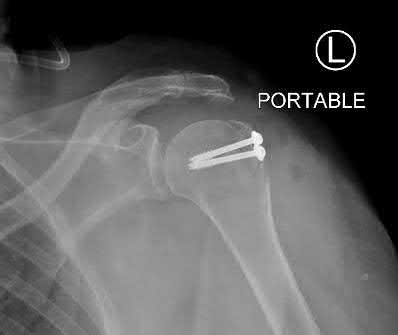

A 55-year-old active female undergoes a primary total hip arthroplasty. The surgeon opts for a ceramic-on-ceramic bearing surface to maximize longevity. Which of the following complications is uniquely associated with this specific bearing couple compared to metal-on-polyethylene?

Explanation

Squeaking is an audible complication unique to hard-on-hard bearings, specifically ceramic-on-ceramic (CoC) total hip arthroplasties. It occurs in up to 10% of CoC THAs and may be related to component malposition, edge loading, or microseparation. Trunnionosis and galvanic corrosion are associated with modular junctions (like a metal head on a metal stem). Pseudotumors are classically linked to metal-on-metal bearings.